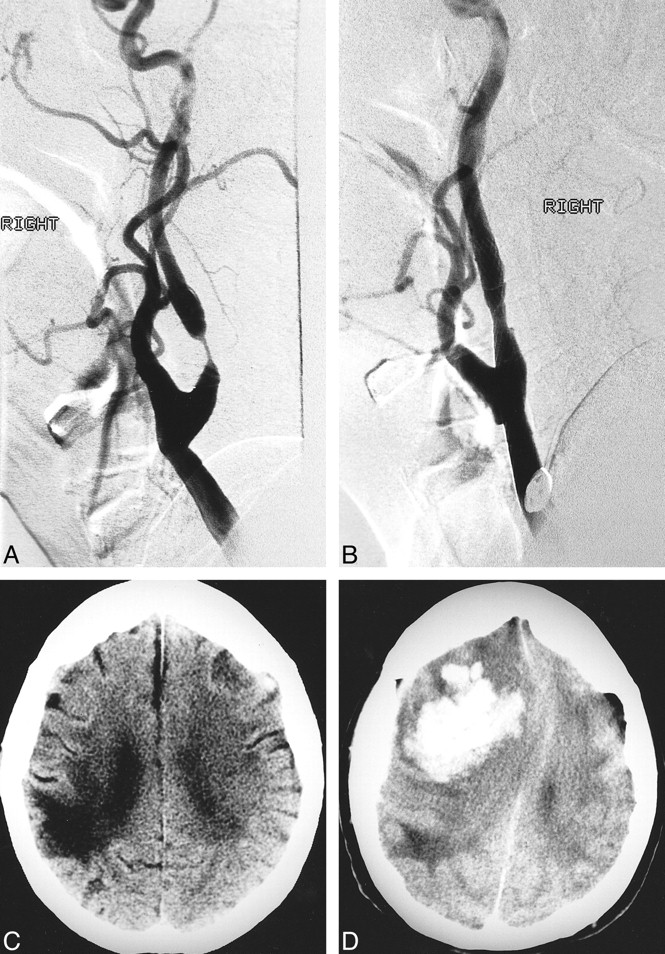

Patient 4. A, Ninety-five percent right internal carotid artery stenosis.

B, Post angioplasty and stenting with no significant residual stenosis.

C and D, Angiogram immediately post stenting demonstrates extravasation from a lenticulostriate artery (arrow). At no time during the procedure did a catheter or guidewire enter into the intracranial circulation.

E, CT of head postoperatively shows a right basal ganglia, intraventricular, and subarachnoid hemorrhage as well as hydrocephalus.